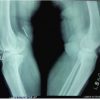

A 5-year-old boy comes to the emergency room of our hospital a week after trauma to his right leg during kindergarten activities, falling with his leg turned backward. Immediately after the trauma, he was taken to the hospital closest to his home, where an X-ray of the entire femur was performed. Despite the clear X-ray findings (Fig. 1a), the patient was discharged with the diagnosis of contusion of the thigh and with the therapy of functional rest and analgesics, when needed.

Due to the persistence of the symptoms, the patient after a week was taken to the emergency room of our hospital, where he presented the right lower limb internally rotated and shortened. An X-ray was then repeated confirming the diagnosis of hip dislocation (Fig. 1b).